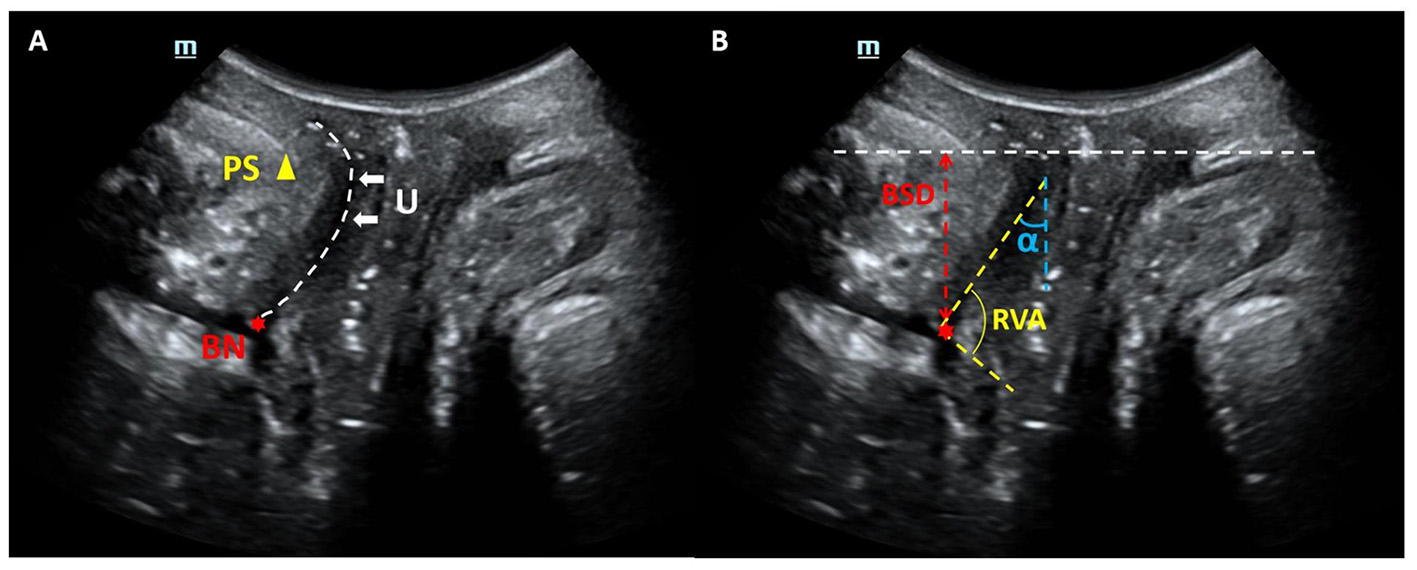

TPUS examinations were conducted by expert sonographer with 5–10 years of the pelvic for ultrasound experience using a Mindray Resona 8 ultrasound system equipped with a DE10-3U 3D volumetric probe (frequency range: 3–10 MHz). Patients were positioned in the lithotomy position after bladder emptying, following the protocol established by Dietz HP (15). Mid-sagittal pelvic floor static images were obtained at rest and during the Valsalva maneuver. Key parameters, including bladder symphyseal distance (BSD), urethral axis angle (α angle), and retrovesical angle (RVA), were measured. Additionally, bladder neck descent (BND) and urethral rotation angle (URA) were calculated. Ultrasound static images were exported in JPG format for subsequent analysis (Figure 2).

Figure 2

Mid-sagittal ultrasound images of the pelvic organs. (A) Anatomical landmarks: the public symphysis (PS), bladder neck (BN), and urethra (U) are also visualized. (B) Index measurement mark: bladder symphyseal distance (BSD), urethral axis angle (α angle) and retrovesical angle (RVA).